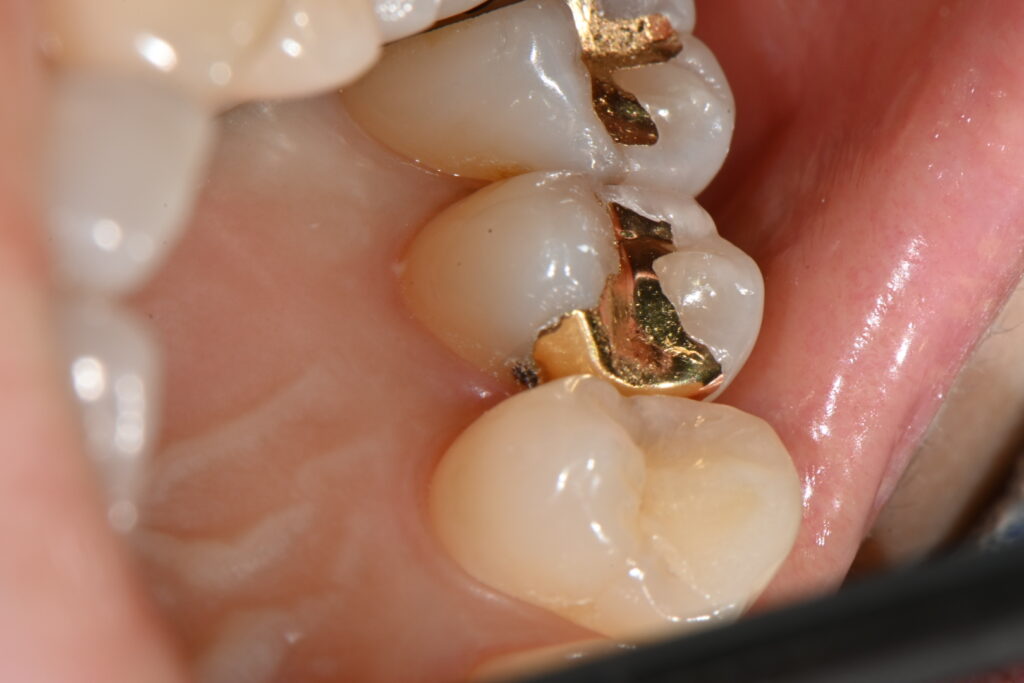

위 사진을 보면 인레이 하방으로 파절선이 내려가는게 보입니다

이게 바로 인레이 치료의 가장 큰 문제점인데요

인레이 치료의 장점은 치료방법이 쉽고 그리고 나름의 강도가 보장됩니다

특히나 금으로 하는 골드 인레이 치료의 경우

치아 범위가 넓은 경우 많이 사용되어 왔지요

하지만 그 인레이 치료는 시간이 지나 인레이에 힘이 가해지면

저렇게 인레이 하방으로 충치 혹은 파절선이 생기게 됩니다.

화살표 부위의 크랙라인

kakaotalk 20251106 001834525

저렇게 보이는 미세한 부위가 보이시나요

저 부분이 바로 인레이의 미세 크랙입니다

골드 인레이의 대표적인 단점이지요

금으로 만든 수복물은 굉장히 장점이 많지만

저렇게 미새한 크랙 라인을 형성합니다

물론 저런 크랙이 모두 문제가 되지는 않지만

시간이 지날수록 점점 커져서 문제의 여지가 될 가능성이 많지요

인레이와 치아의 들뜸

인레이 치료후 인레이와 치아사이의 경계부분

사진을 보시면 인레이와 치아사이에 경계가 보입니다

저 경계부분은 나중에 음식물이 저류하고

세균이 번식할 환경을 만들어 줍니다

그리고 이차충치로 이어지게 되는것이지요